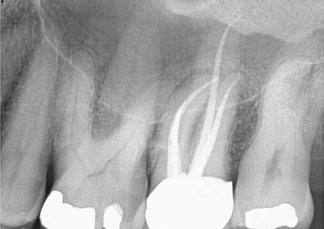

on the crest of the ridge in the region of teeth Nos. 15-25. While creating the incision, bleeding was noticed in the region of tooth No. 15 which intensified during the flap reflection (Figure 2). Bleeding was pulsatile, indicating an arterial bleed. Initially attempts to control bleeding included a pressure pack and ice pack, and the bleeder was isolated, and the vessel ligated (Figure 3). The bleeding could be controlled, and the procedure was completed by placing four Bioner implants (Bioner, Spain), size 4/10 mm. Sutures were placed, and patient was kept on basic medication for pain and infection control. Immediately after the surgery, the patient was advised to get a CBCT. As shown in Figure 4, a coronal view and Figure 4B (yellow arrows), the position of the artery can be seen.

Figure 1: Pre-op panoramic radiograph Figure 2 (left): Alveolar antral artery (AAA). Figure 3 (center): The artery has been ligated with suture. Figures 4A and 4B (right): CBCT post-implant placement and position of the artery coronally (top). 4B. Showing the position of alveolar antral artery (AAA) in relation to implant placement as indicated by the yellow arrows (bottom)